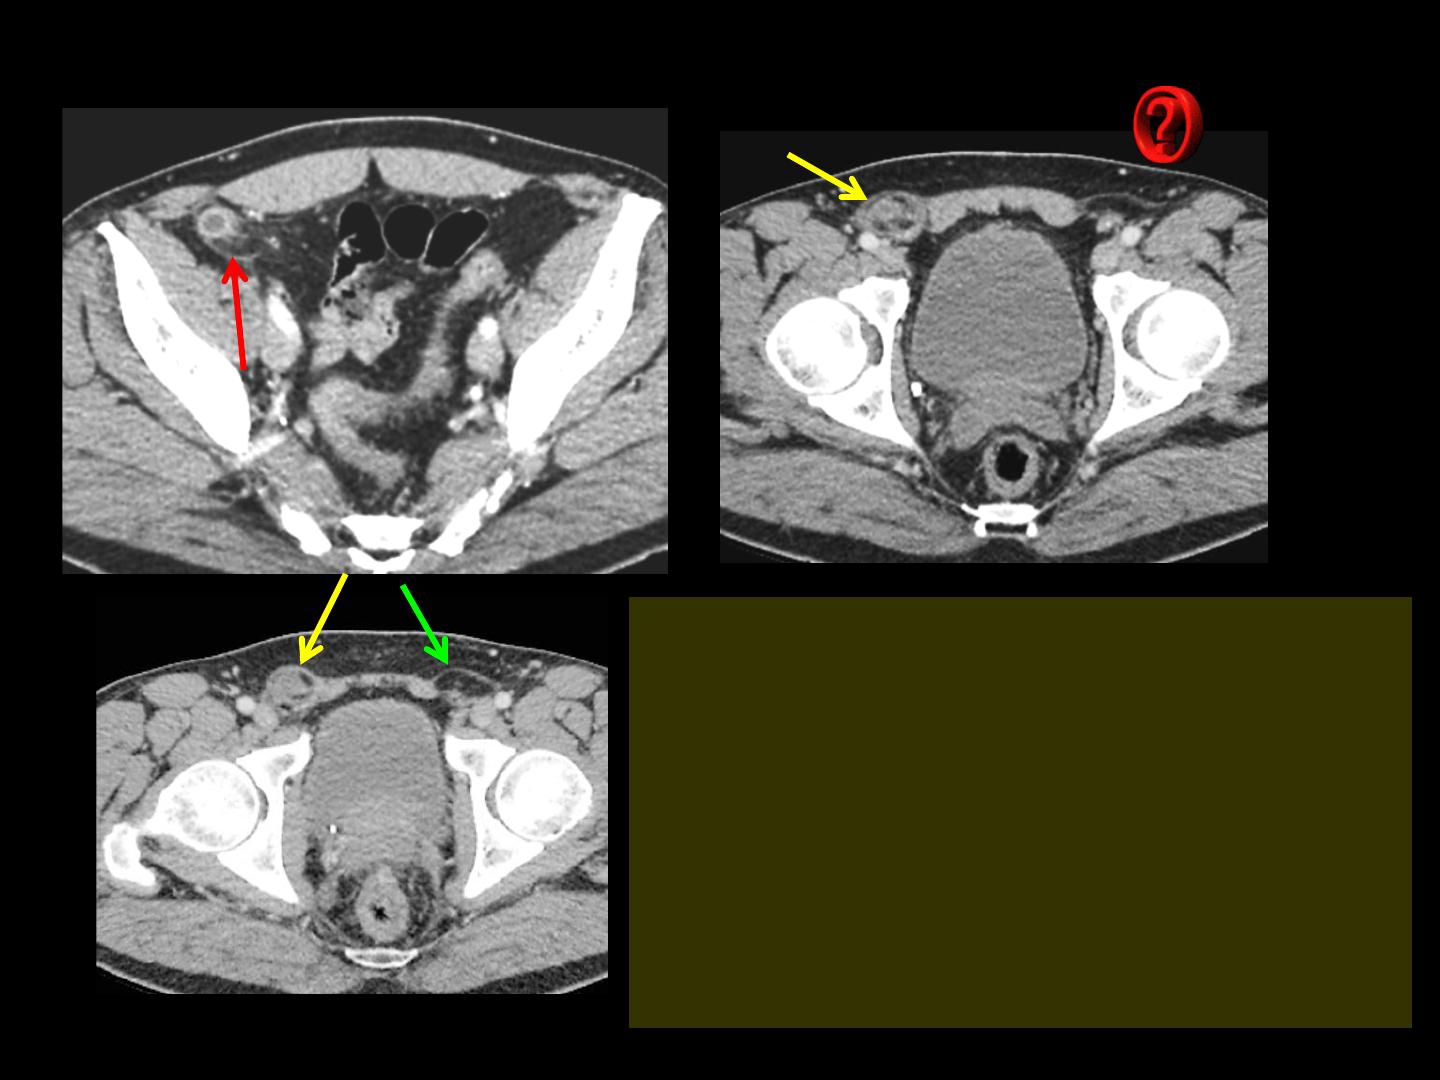

Quels sont les éléments sémiologiques significatifs à retenir sur ces images

-présence d'une tuméfaction de la région inguinale

droite , à contenu hétérogène, tissulaire et graisseux

-sur la coupe de la fosse iliaque , présence d'une

structure tubulaire, à parois épaisses avec

rehaussement intense et persistant, infiltration du

péritoine adjacent correspondant au méso

appendiculaire

-du côté controlatéral, présence d'un petit lipome

pré-herniaire confirmant l'existence de hernies

inguinales obliques externes bilatérales